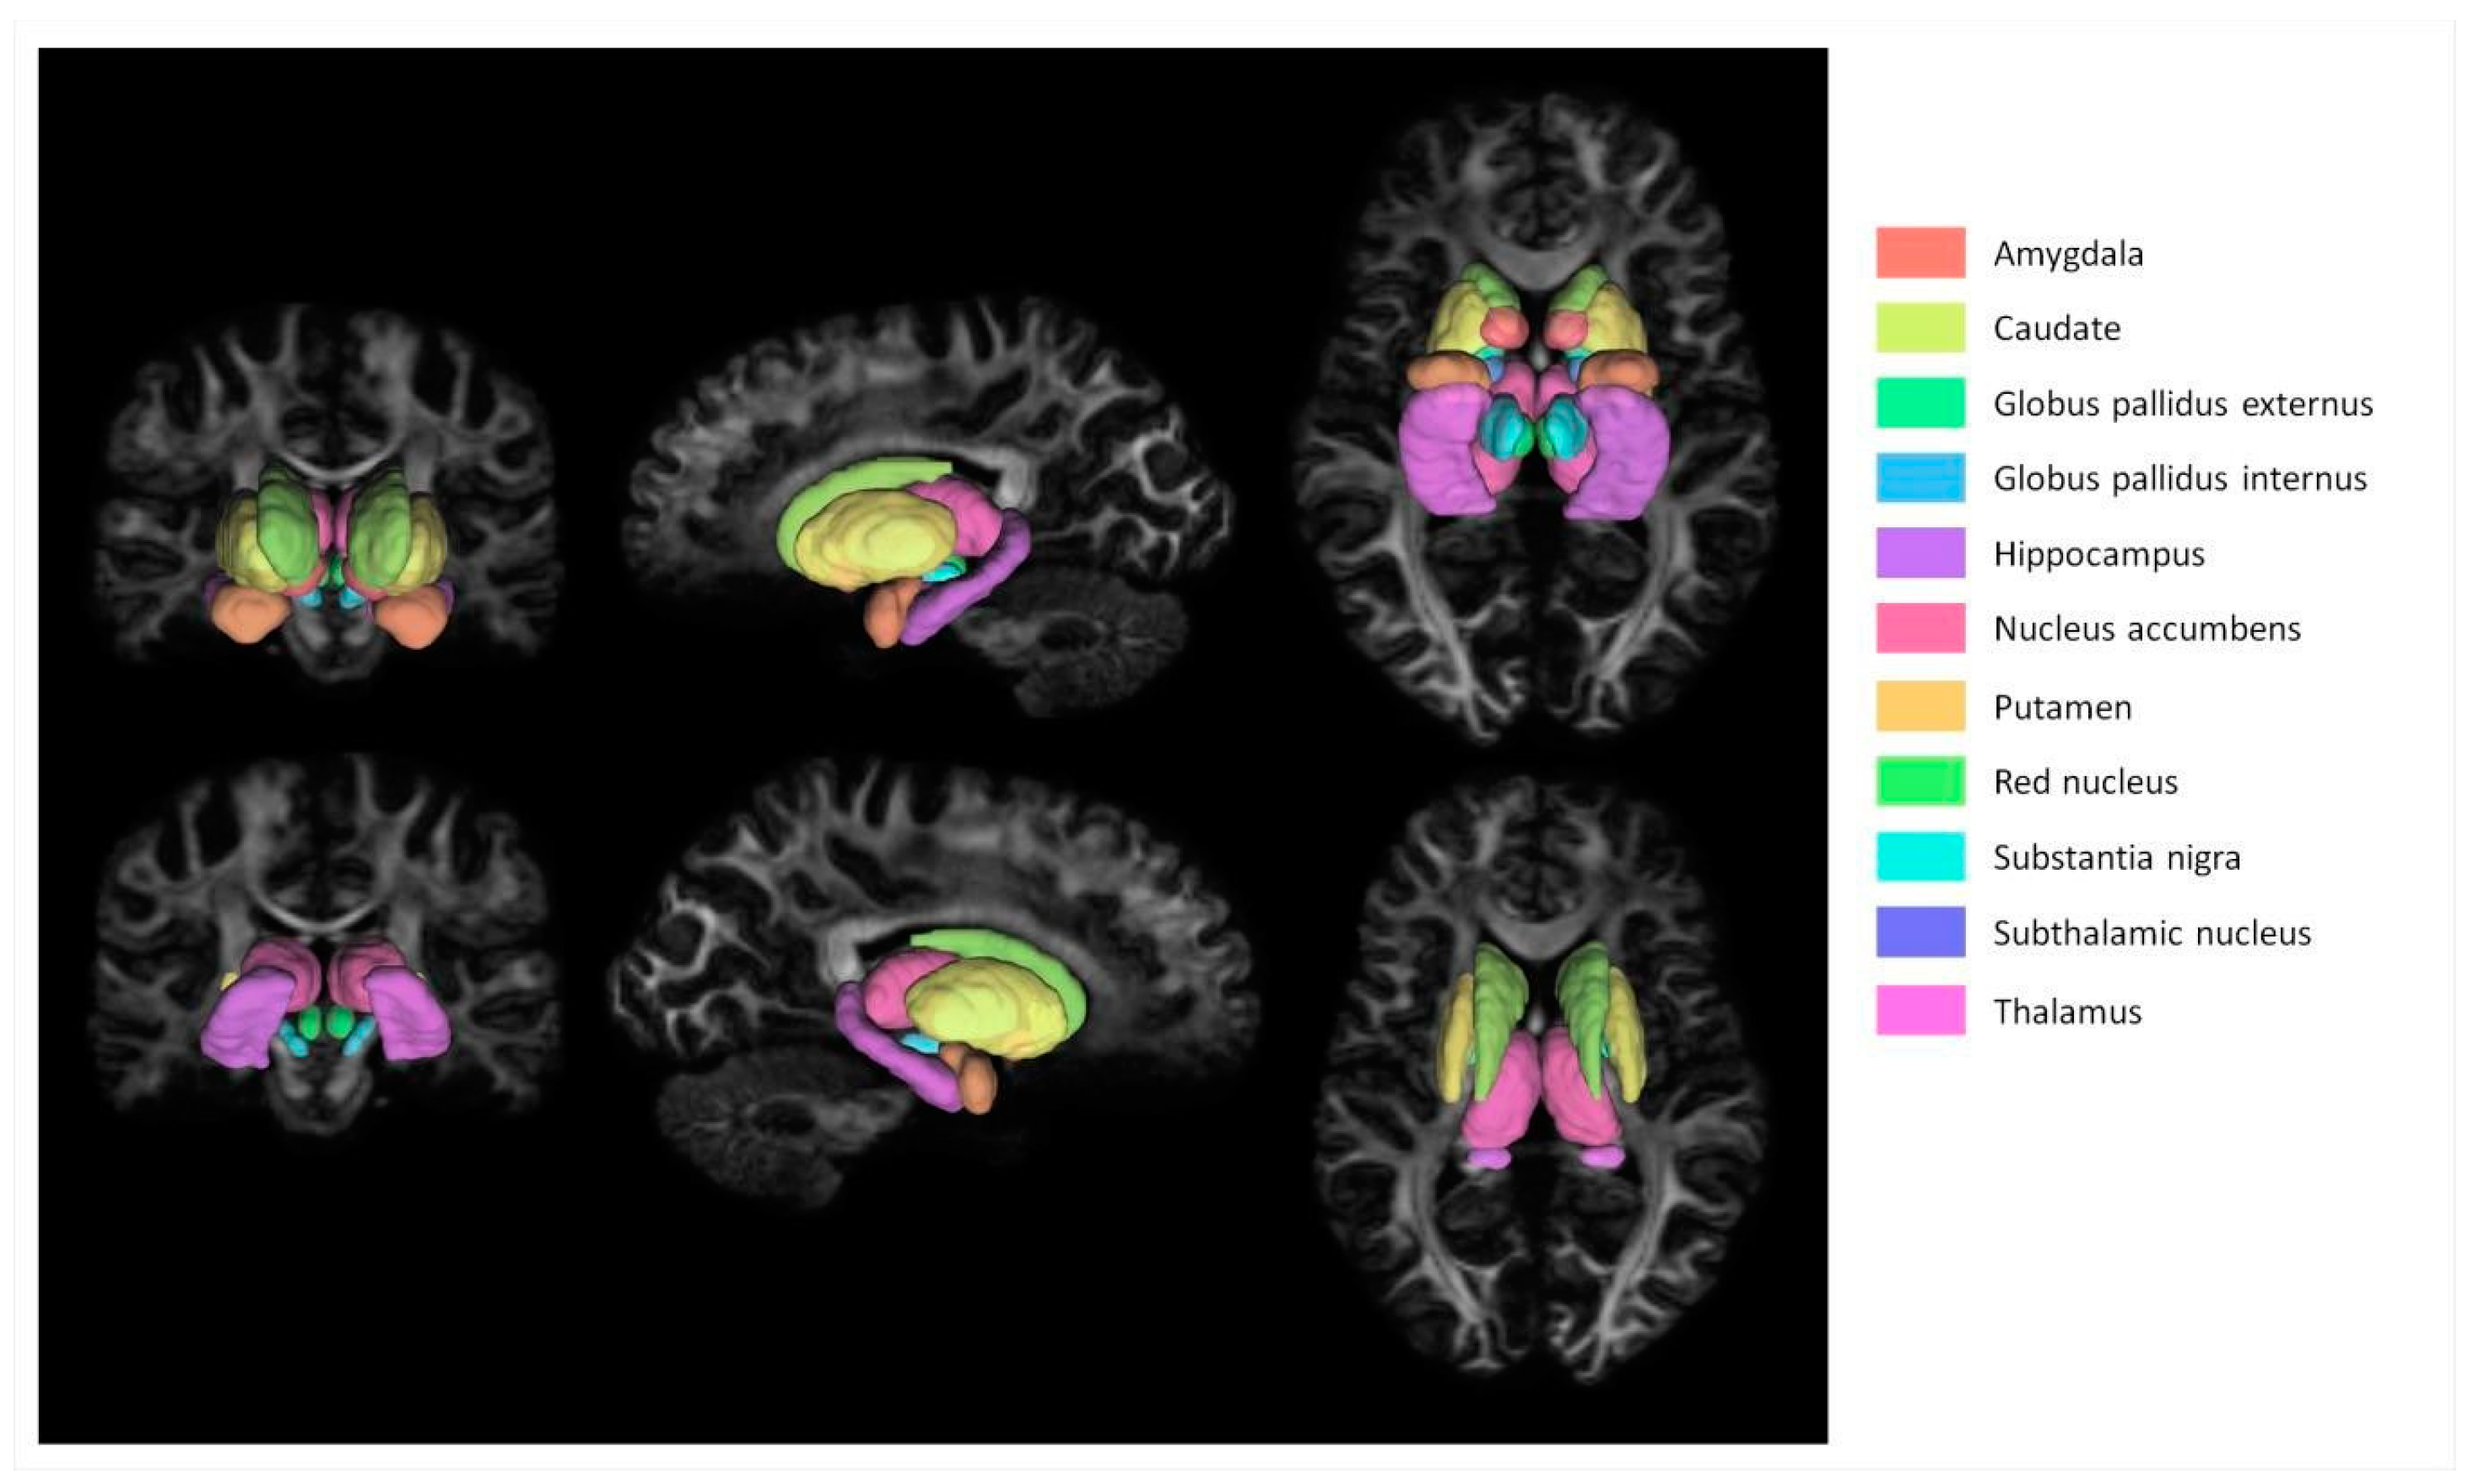

2.3. Image Processing